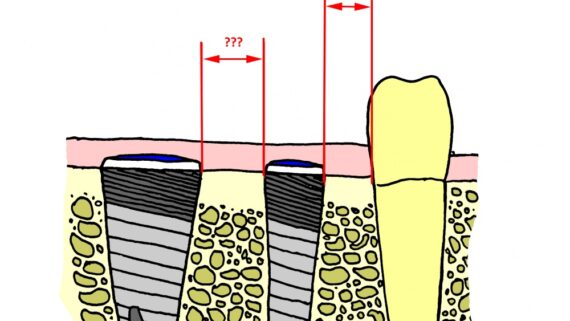

Я планирую установить имплантат Friadent Xive диаметром 4,5 мм, что максимально соответствует размеру зубов пациента. Обратите на положение аналога абатмента по отношению к соседней четверке. Это очень важный момент.

Точно также делаем разметку и готовим лунку под имплантат седьмого зуба. Планируемый диаметр импланта — 5.5 мм:

Большое, очень большое значение для качественного протезирования играет правильный подбор и позиционирование имплантов. Поэтому утверждать, что в протезировании все зависит от ортопеда и зубного техника — не вполне корректно.